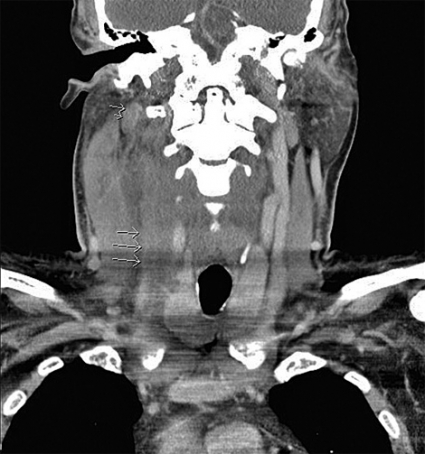

Patientens tillstånd försämrades under de följande dagarna. Takypné och hypoxi (91 procent trots 3 liter syrgas på grimma) noterades. DT-undersökning med kontrast påvisade förekomst av trombos i vena jugularis interna dextra (Figur 1) och lungembolier och pleuravätska.

Patienten erhöll nu antitrombotisk behandling i form av dalteparin (12 500 IE dagligen), och tidigare tillförda antibiotika byttes mot piperacillin kombinerat med tazobaktam. Efter detta förbättrades patienten ånyo gradvis. Förhöjda levervärden och trombocytos noterades, medan övriga rutinprov normaliserades inom den närmaste veckan.